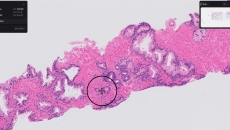

The partnership will initially be used to distribute PathAI’s research-use-only algorithm focusing on immuno-oncology.

IntelliSite is designed to streamline workflows, enhance diagnostic confidence, facilitate collaboration, integrate AI and increase the efficiency of pathology labs.

Paige Prostate analyzes digitized biopsy slides and identifies areas that could be cancerous for the pathologist to review further.